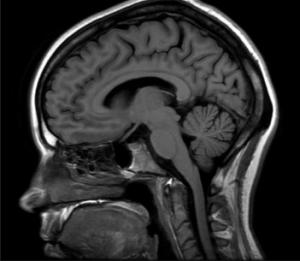

El médico boricua viaja alrededor del mundo para atender a niños con condiciones cardíacas en países subdesarrollados. Mientras muchos realizan los preparativos para disfrutar sus vacaciones, el doctor Enrique Carrión se prepara para atender a niños con condiciones congénitas cardíacas en países subdesarrollados. “Los defectos congénitos del corazón son el asesino número uno entre todos…